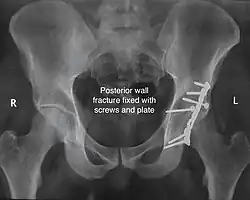

Posterior wall fracture fixed with screws and plate -

Function after fixation